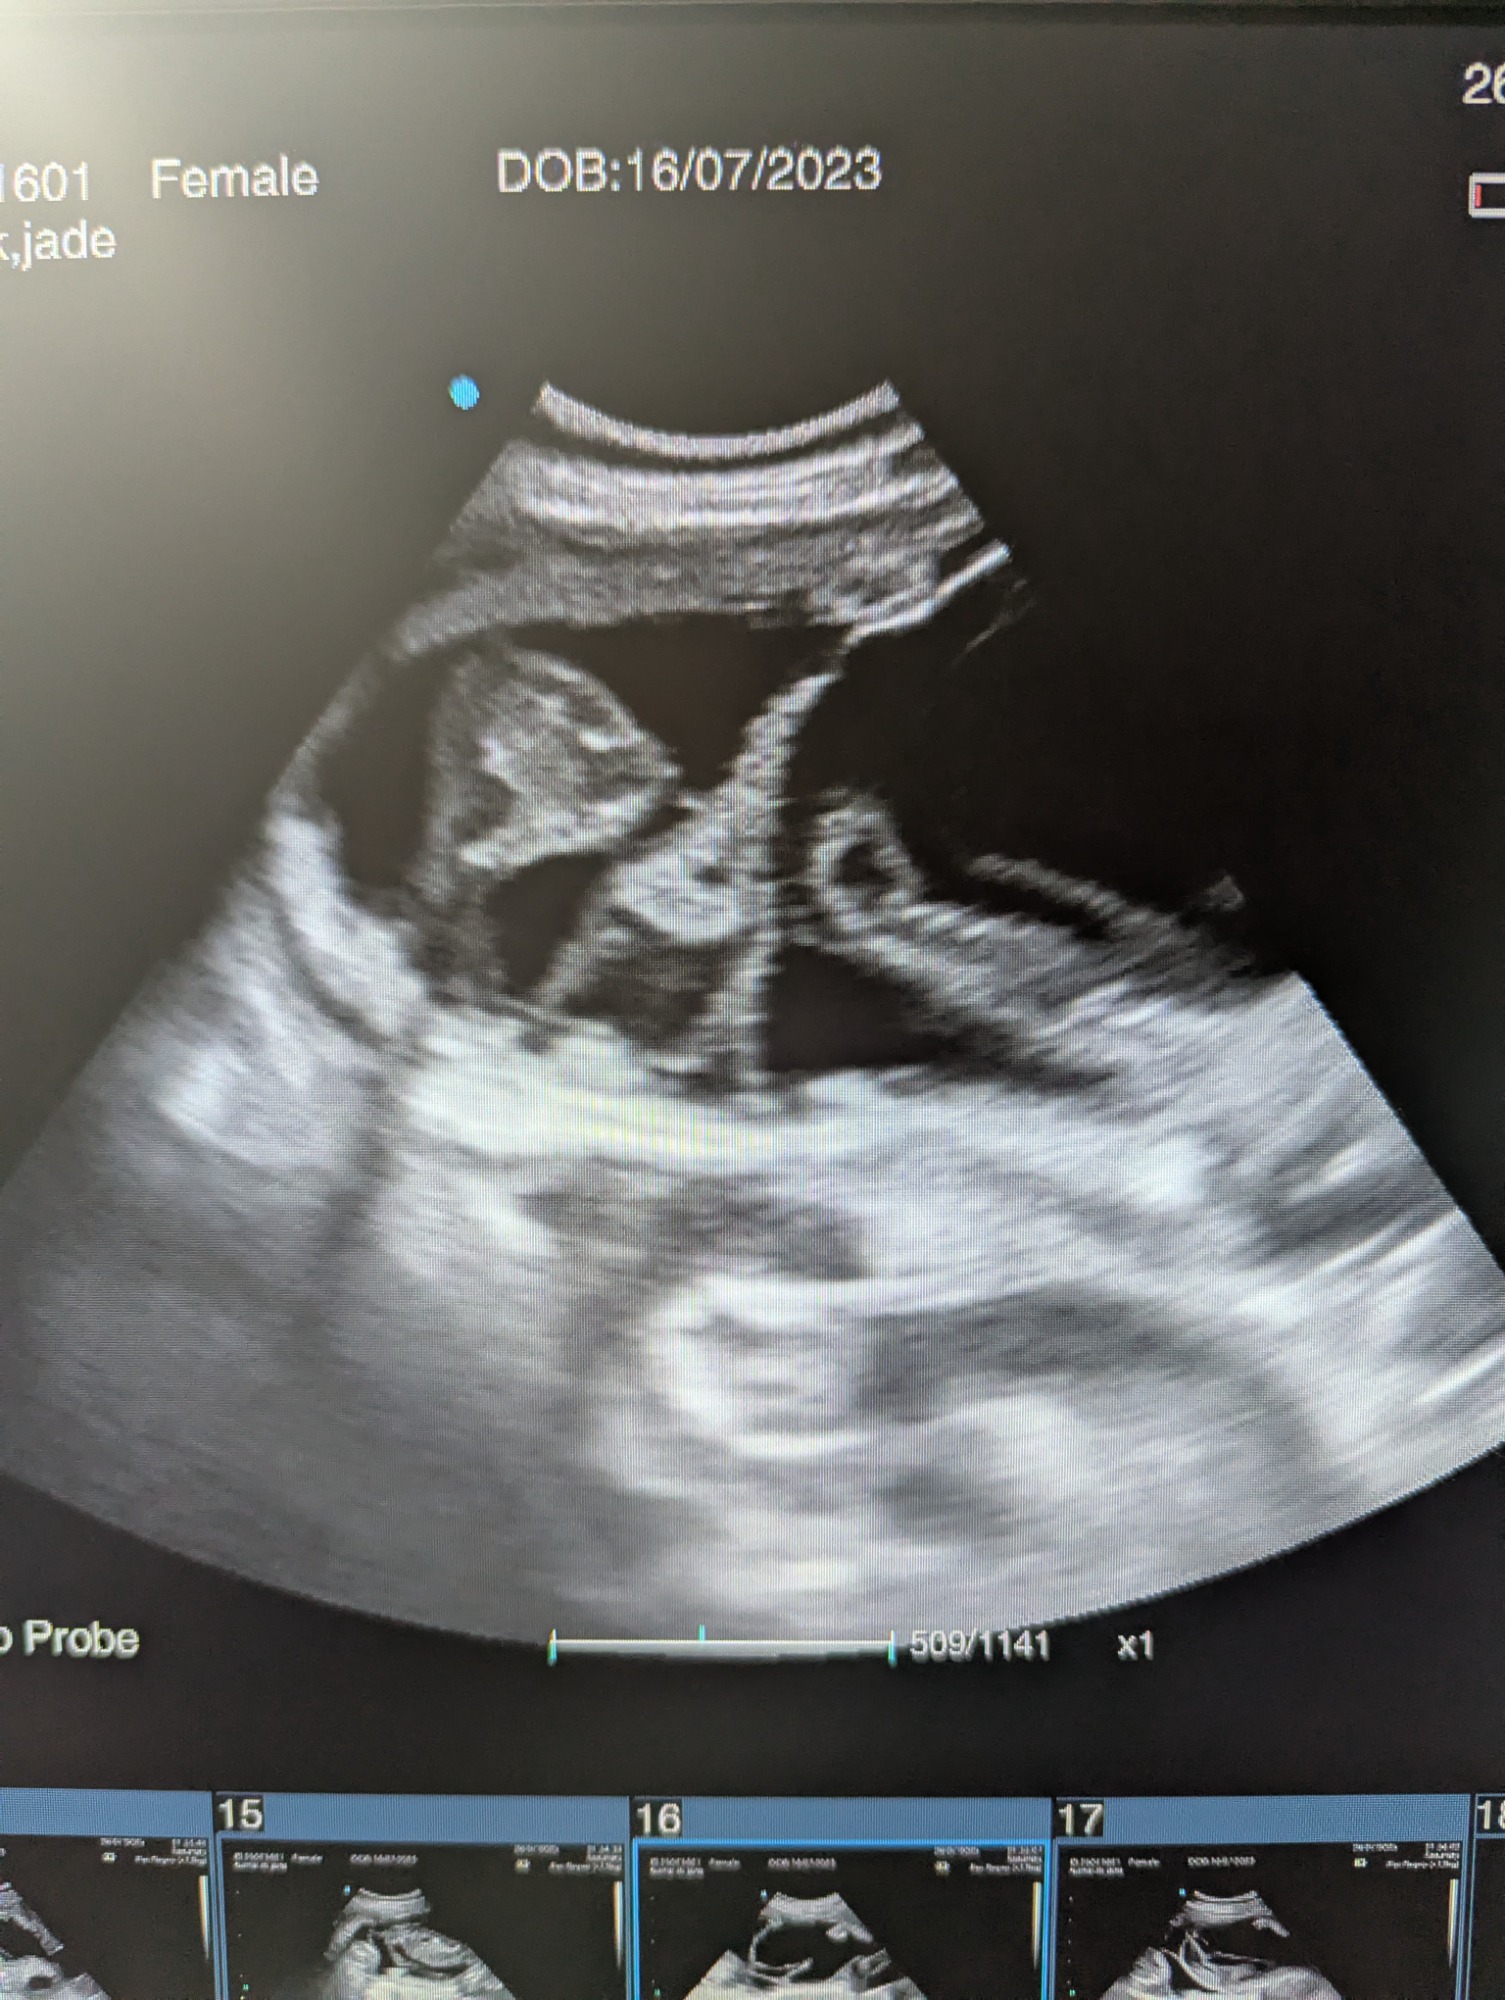

Ultrasound pregnancy scanning is a safe, non-invasive way to confirm pregnancy in dogs and cats, offering breeders and pet owners peace of mind and vital information to support responsible care. It allows us to detect gestational sacs, assess foetal development, and estimate litter size—all while ensuring the wellbeing of the animal.

For the most accurate and reliable scan, we advise booking between Day 25 and Day 32, when pregnancy is more easily confirmed and foetal structures are clearer. If an early scan is performed and no pregnancy is detected, we offer a FREE complimentary re-scan after 7 days at the clinic to ensure clarity and support informed decision-making.